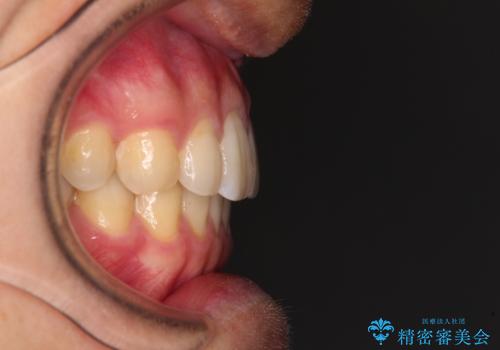

前歯のクロスバイトと抜歯が必要な奥歯の虫歯 インビザラインとインプラント治療

- 前歯のクロスバイトと、大学生のころから放置している虫歯を気にして来院された患者様です。

マウスピースでの矯正治療を希望されていましたが、前歯のクロスバイトは不十分な仕上がりや歯髄壊死などのリスクが高くなるため、術前にワイヤーで大まかに整えてからインビザラインにて矯正治療を行うこととしました。